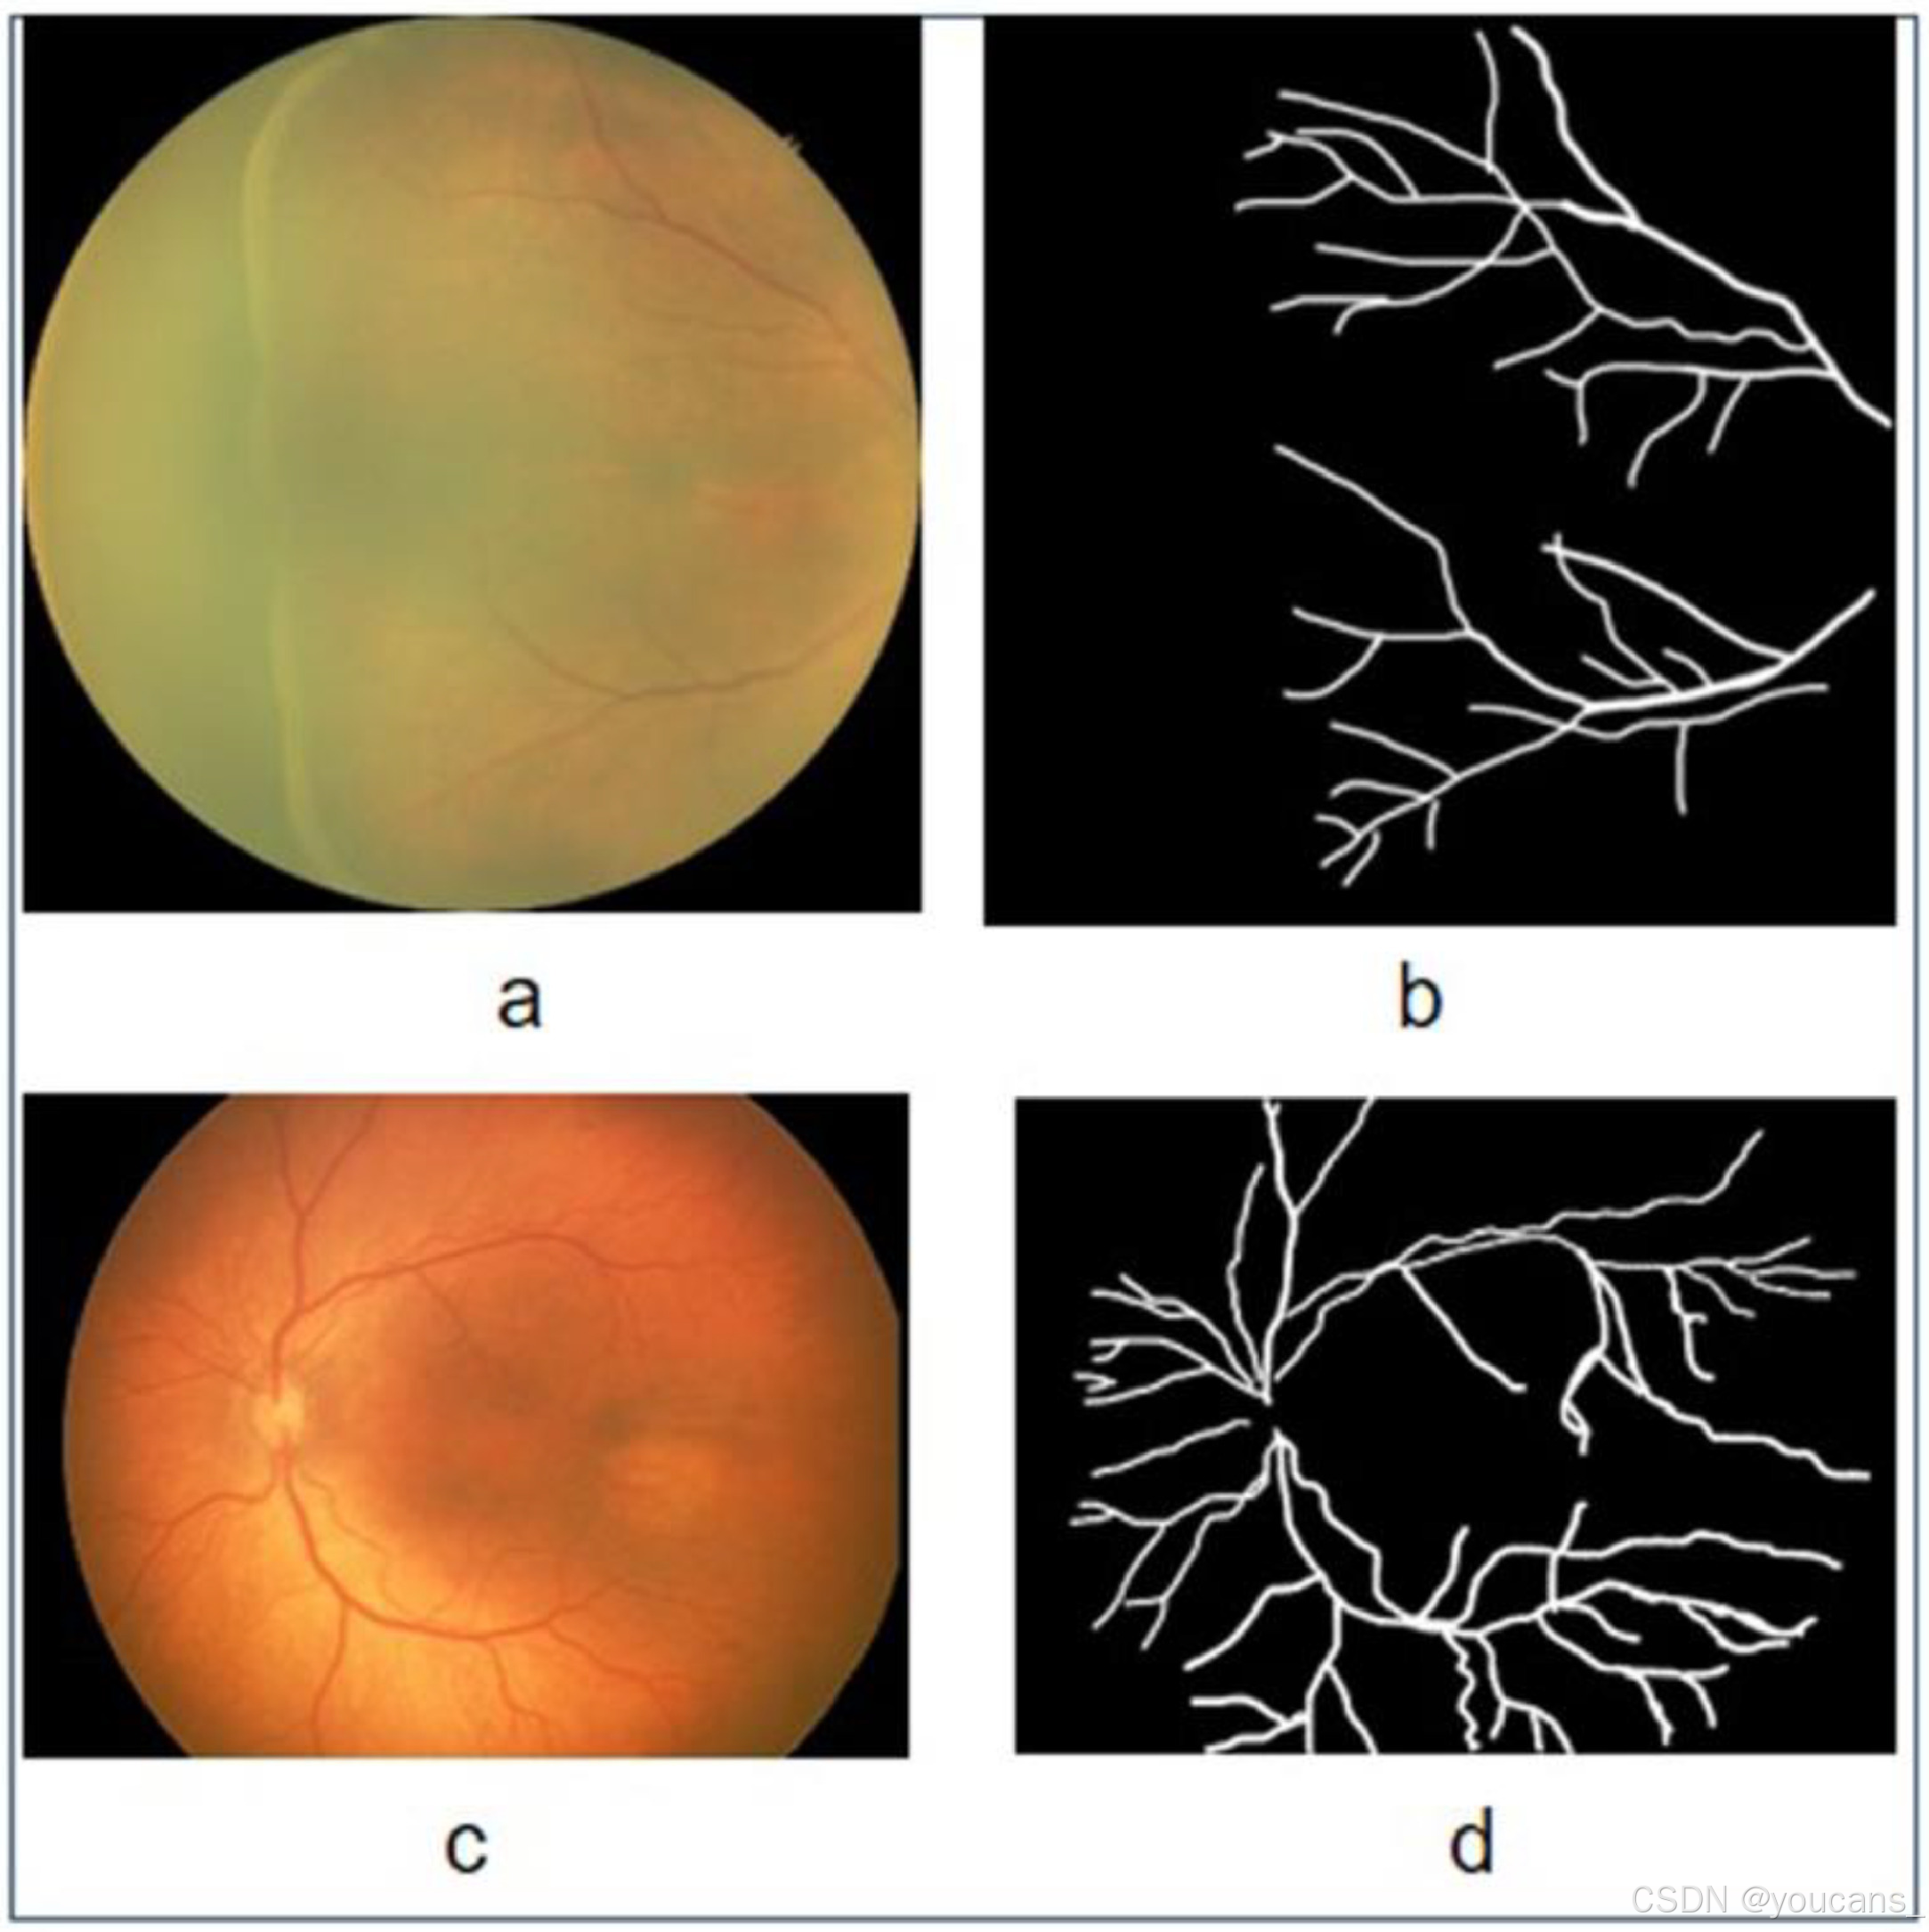

3.4 血管分割图像

HVDROPDB-BV 数据集 用于 视网膜血管(Blood Vessels) 的分割。

选取 100 张图像创建 HVDROPDB-BV 数据集,这些图像来自于 后部视图(posterior view) 和 颞视图(temporal view)。如图5所示,每张图像都有对应的分割掩膜图像(Ground Truth),即血管的分割掩膜(masks)。

HVDROPDB-BV 数据集用于 视网膜血管的分割,包含4 个子集,每个子数据集各有50幅图像。

- RetCam_Vessels_images:通过 RetCam 成像系统 捕获的视网膜血管图像。

- RetCam_Vessels_masks:与 RetCam 对应的血管掩模图像。

- Neo_Vessels_images:通过 Neo 成像系统 捕获的视网膜血管图像。

- Neo_Vessels_masks:与 Neo 对应的血管掩模图像。

图5:血管分割的原始图像和掩模图像:(a)Neo 原始图像,(b)Neo 掩模图像,(c)RetCam 原始图像,(d)RetCam 掩模图像。